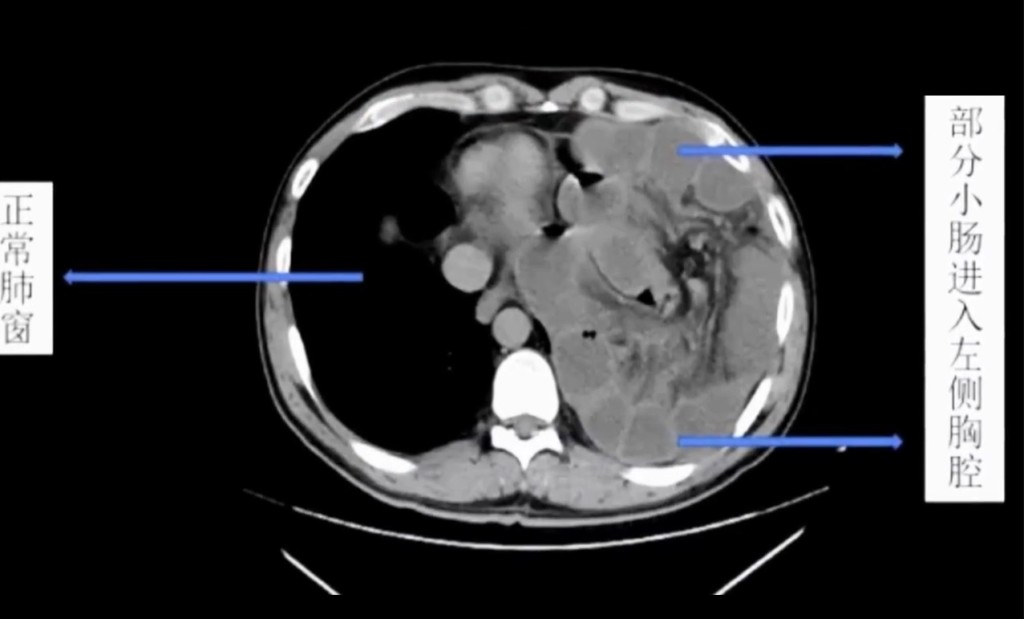

醫院腸胃外科主任邱磊表示:「病患是坐著輪椅來的,腹痛難忍,地方醫院已經替他打了兩隻強力的止痛藥,但疼痛仍無法緩解,到院時已經全身冰涼,雖然神智仍然清楚,但已經出現休克的徵兆,左肺的呼吸聲完全消失」,院方立刻替他進行電腦斷層掃描(CT Scan),「片子顯示左肺已經全都被壓縮扁了,左邊胸腔裡全都是白白的東西」,研判是男子的小腸。

邱磊表示,男子曾罹患結腸癌,當時手術切除掉部分的膈肌(diaphragm),「但修補的部位沒有天生的那麼堅固」,患者經常健身,加上愛喝酒常嘔吐,腹腔壓力變化大,造成膈肌破裂,「長達2米的小腸就從破裂的位置鑽進胸腔」,形成醫學上的「橫膈疝氣」(diaphragmatic hernia,膈疝)。

由於小腸的擠壓,男子左邊的肺已經被頂到嚴重萎縮,小腸堆積充血的結果也導致壞死與內出血,最後經過緊急手術切除,才脫離險境,但原本長約6米的小腸,只剩下約4米。